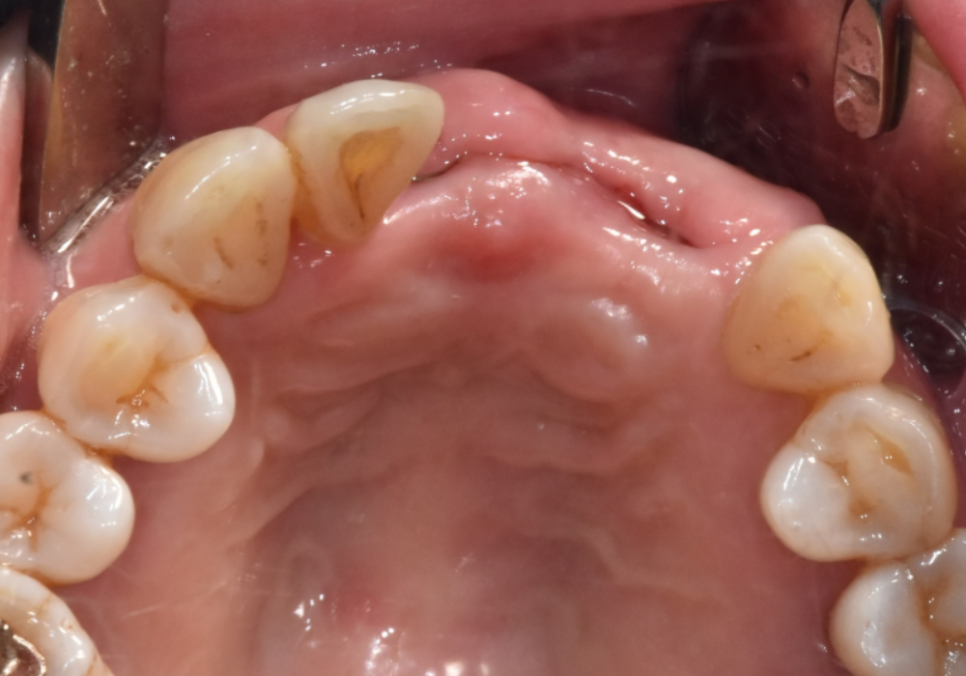

뼈이식을 동반한 임플란트 수술

고덕동 임플란트, 튀어나온 앞니, 비용은 줄이고 자연스럽게 개선한 실제 사례

방사선 사진상, 뿌리끝 염증으로

뼈가 녹은 부위가 있었고,

뼈 폭도 얇아 임플란트만 식립하기엔

무리가 있어 보였습니다.

231107

그래서 뼈이식과 함께

임플란트 수술을 진행하는 것으로

계획을 세웠습니다.

뿌리끝 염증이 있던 케이스는

염증 조직(육아조직)을

남기지 않는 게 정말 중요합니다.

이 염증조직들을

제대로 제거하지 않으면

애써 심어 놓은 임플란트도

이 녀석들 때문에

뼈가 녹아 문제가 생기거든요.

그래서 잇몸을 절개한 뒤

염증 조직을 직접 눈으로

확인하며 깔끔하게 제거했고,

깨끗해진 뼈에

뼈이식을 충분히 시행했습니다.